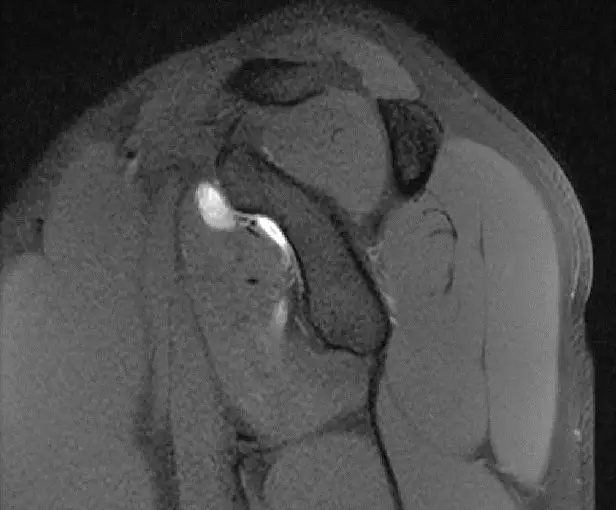

这张片子可以看到上盂唇及肱二头几件长头止点,盂唇高信号的特点,质地比较均一,相对比较尖锐,边界比较清楚

此片可以看到冈上肌腱。